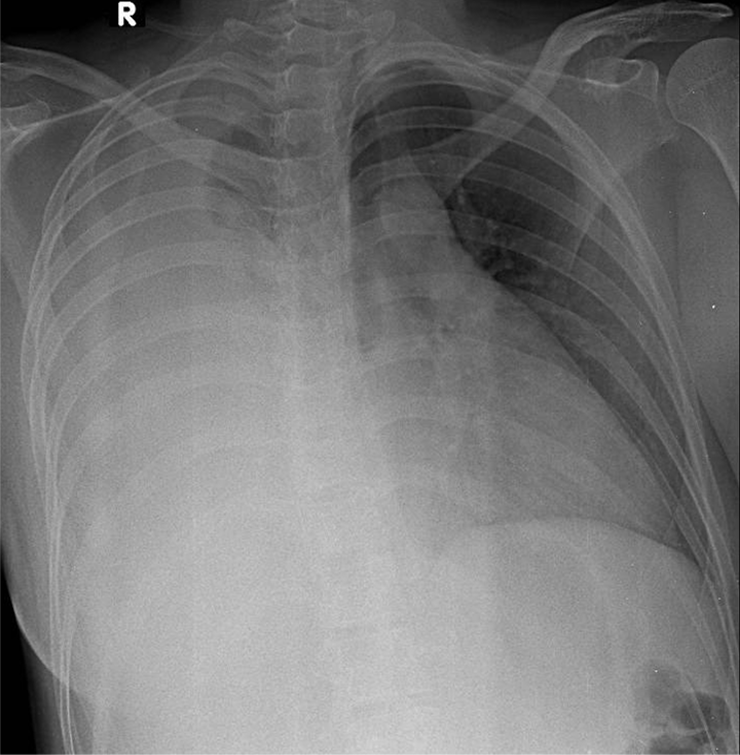

Hãy phân tích tình huống Nữ 54 tuổi -CĐ:Tràn dịch màng phổi (P) lượng nhiều nghi do lao

1-Khí quản lệch (T) 2-Tràn dịch màng phổi (P) lượng nhiều 3-Bóng tim và trung thất lệch (T)